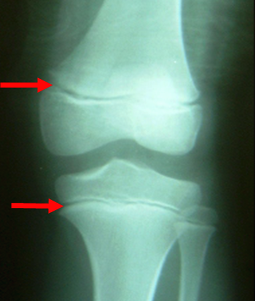

X-ray로 성장판을 검사하면 손이나 골반, 무릎관절, 팔꿈치관절, 발목관절을 사용해서 골연령을 평가하는데요.

성장판 검사는 나이에 따라 검사 부위가 다른데 청소년의 경우 어깨를 같이 찍기도 하고, 1세 미만의 경우 무릎 사진을 같이 찍기도 합니다.

성장판이 닫힌다는 것은 성장판 양쪽 끝부분의 연골이 점점 단단한 뼈로 바뀌게 되는 것을 말하는데요.

성장판은 한 번 단단해지면 다시 연골이 될 수는 없기 때문에 성장판이 닫혔다는 것은 키 성장도 끝났다고 생각하면 됩니다.